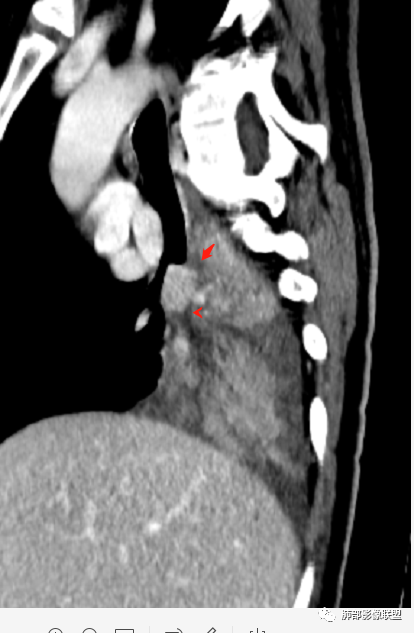

长轴、支气管、血管是观察的重点

这就需要重建

中间段支气管

基底干是外侧朝腔内压迫?还是外侧壁占位突入腔内?

这是肺门淋巴结压迫、侵犯支气管导致堵塞?还是腔内本身肿瘤?

远端支气管是粘液栓

这个问题关系到诊断的问题

首先血管未见明显侵犯、移位,提示病灶:炎性;肿瘤:外朝内——含粘液类腺癌(肺门淋巴结转移),腔内肿瘤(鳞癌、腺癌、类癌、小细胞、粘液表皮等)

腔内肿瘤,远端堵塞

冠状位重建有钻缝的感觉

我再发一些图

这是源头

这些如果单纯不张肯定强化明显